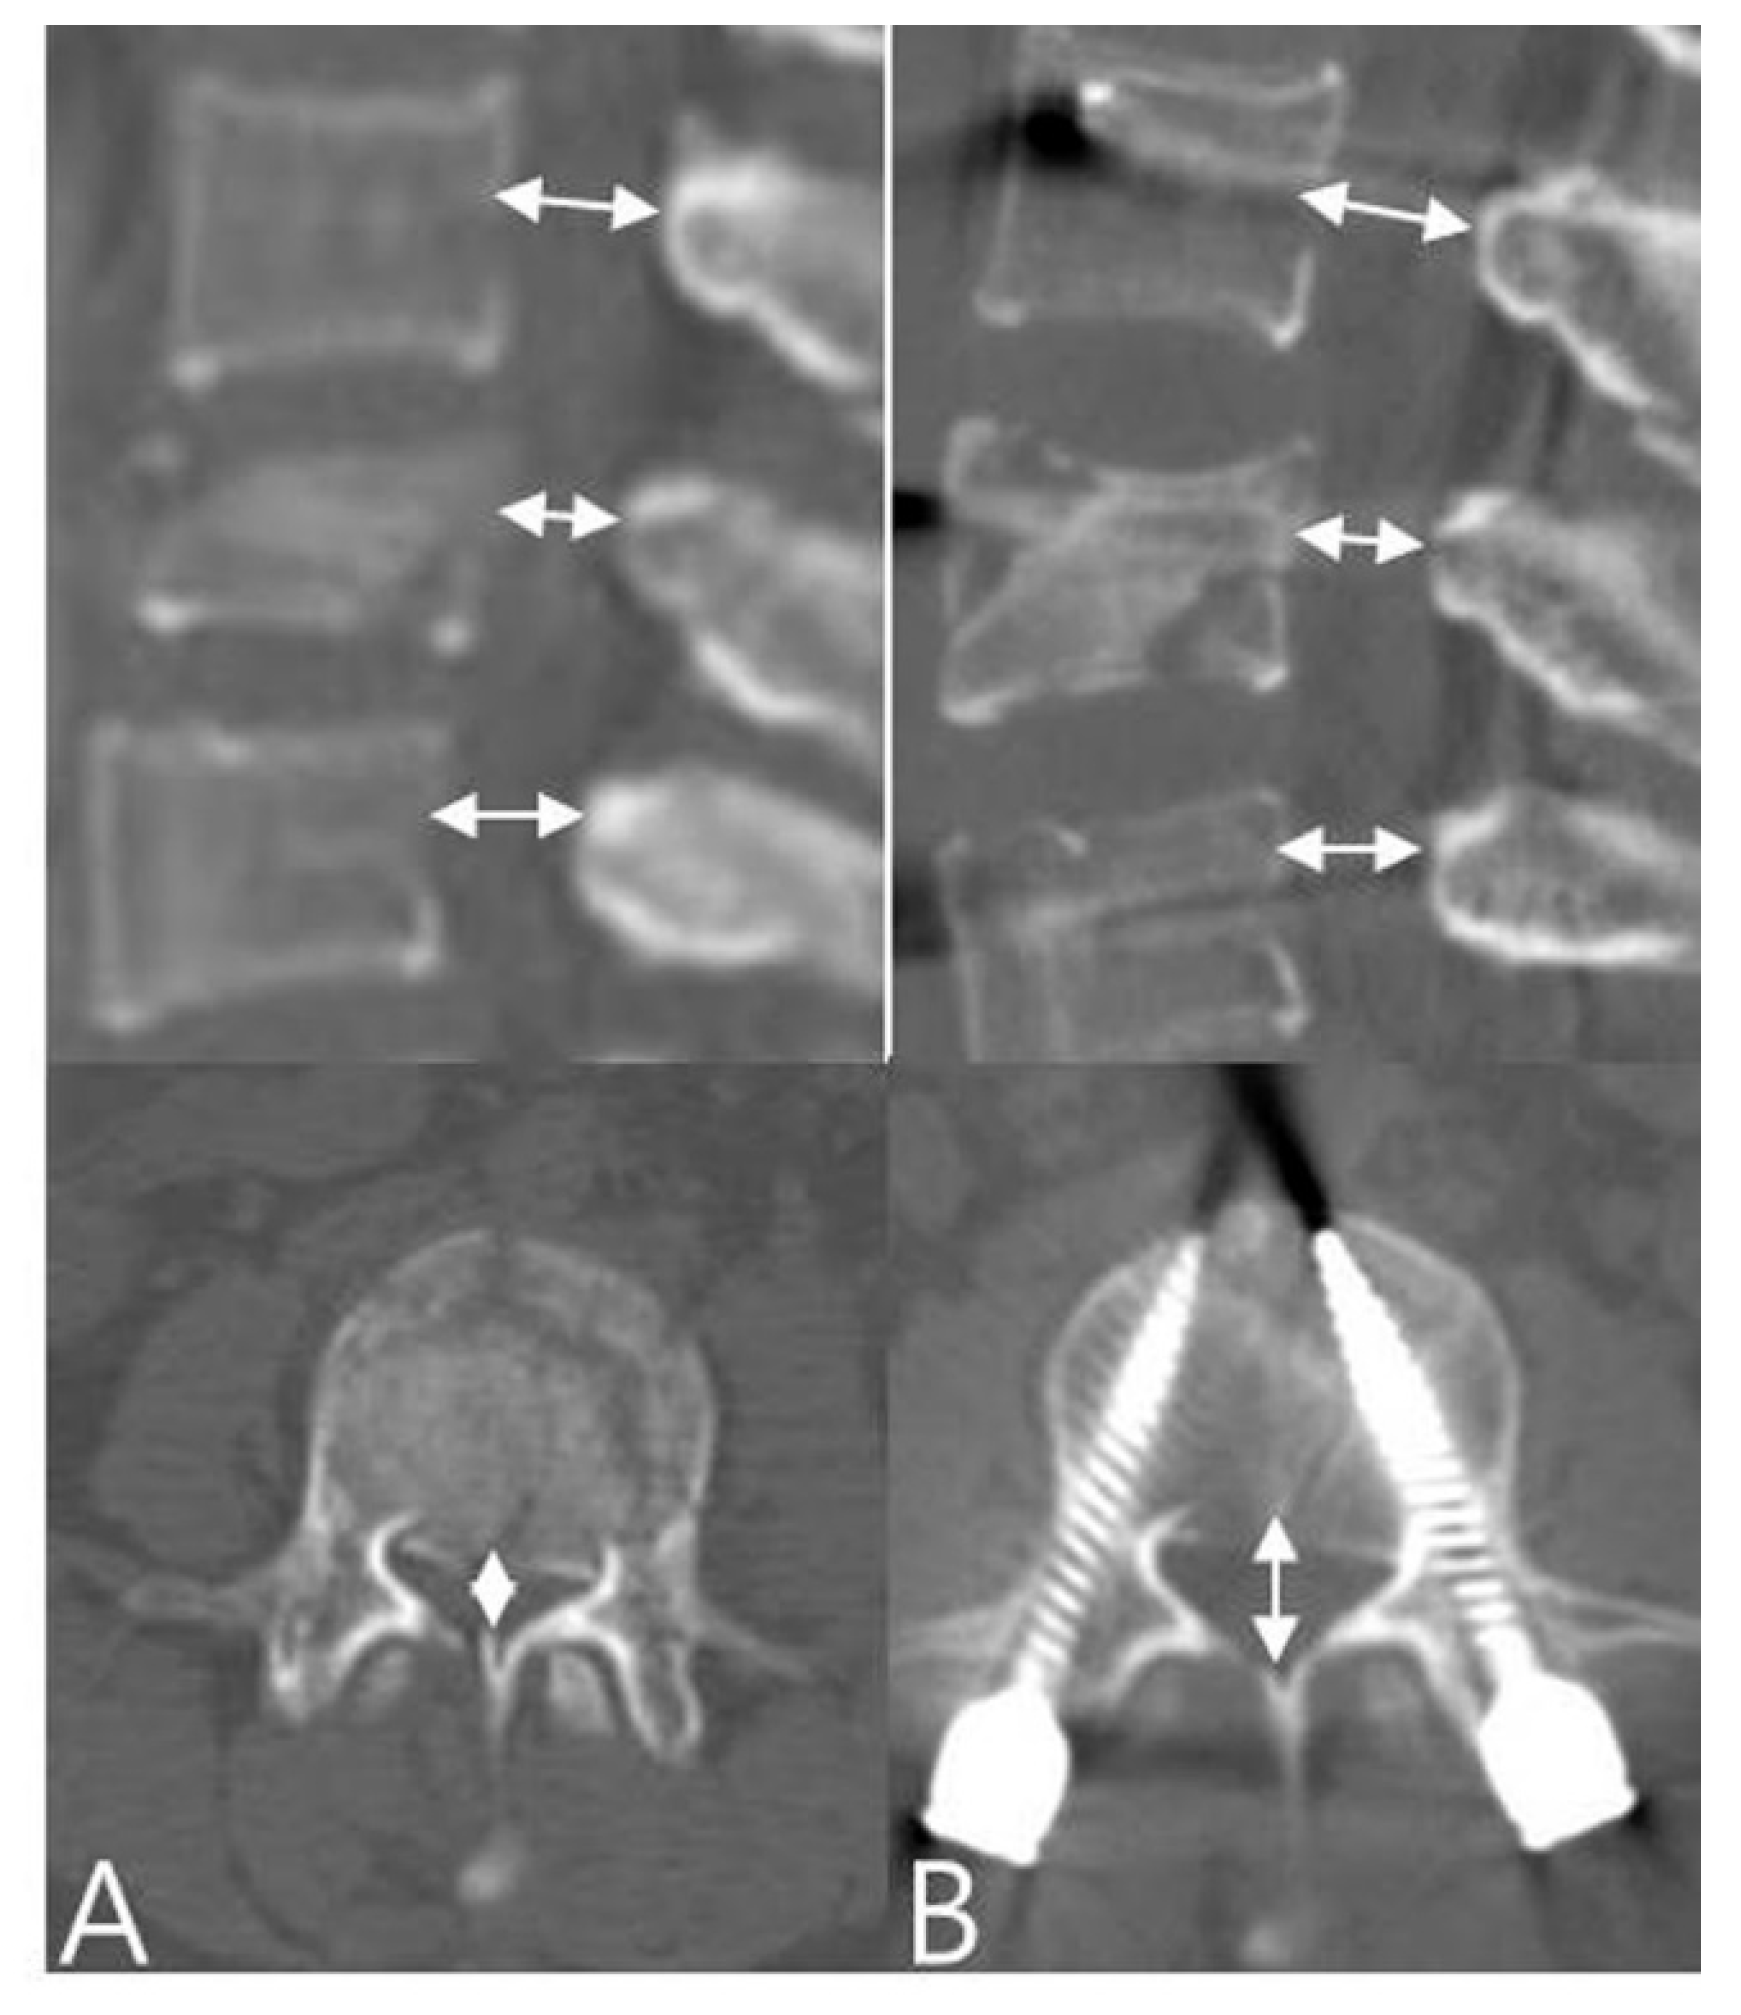

RKA does not only stand for the deformity of the fractured vertebral body, but also the destruction of the affected intervertebral disc. Spinal canal encroachment and clearance were calculated before and after surgery on CT scans. The percentage of canal compromise was calculated with the narrowest mid-sagittal diameter of the injured level divided by the mean of the mid-sagittal diameters of adjacent upper and lower vertebra (Figure 2) [5,18].

Figure 2.

Spinal canal encroachment and clearance were calculated (A) before and (B) after sur gery on CT scans. The percentage of canal compromise was calculated with the narrowest mid-sagittal diameter of the injured level divided by the mean of the mid-sagittal diameters of the adjacent upper and lower vertebrae.